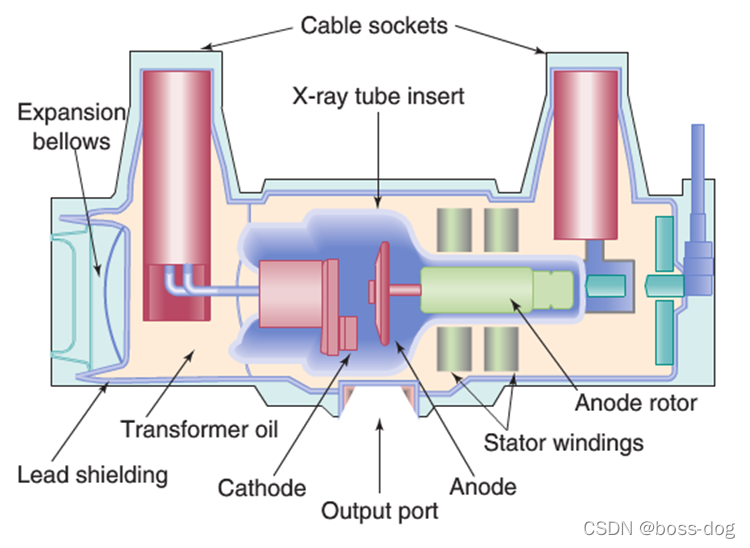

上图中为旋转阳极X射线管:(高能量,高负荷)

主要用于①胸部X光片②CT荧光成像③胸透